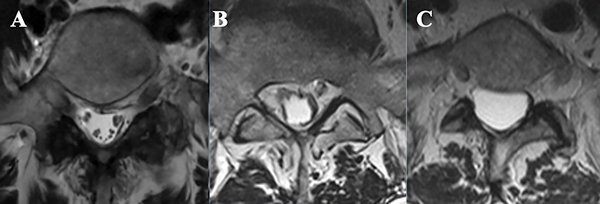

En RMN pueden verse 3 patrones diferentes6,7:

1. Adhesión central de las raíces nerviosas de la cola de caballo en 1 o 2 cordones;

2. Patrón de “saco tecal vacío”: raíces adheridas a las menínges en la periferia, sólo se visualiza la señal de LCR en el saco tecal (Figura 5);

3. Saco tecal lleno con tejido inflamatorio, sin señal de LCR, imagen que se corresponde con el bloqueo de LCR mielográfico.

Otros hallazgos en RMN son aglutinación y/o engrosamiento de raíces nerviosas y formación de quistes aracnoidales (Figura 6).

Figura 5: Cortes axiales de RMN en secuencia T2. A- Canal medular de configuración habitual a nivel lumbosacro; B y C- Signo del “saco tecal vacío”: patrón visualizado en RMN caracterizado por adherencia de raíces nerviosas en la periferia de las menínges.

Figura 6: Imágenes de RMN lumbar en secuencia T2, a nivel L2. A- Configuración habitual del canal medular a nivel lumbosacro, se visualizan múltiples raíces nerviosas. A este nivel las raíces de la cola de caballo se ubican en el saco tecal a nivel dorsal, debido al efecto de la gravedad en el decúbito del paciente; B y C- Aglutinación y distribución irregular de raíces nerviosas, hallazgo característico de la aracnoiditis adhesiva; D y E- Imágenes de RMN de la paciente presentada, donde se observa aglutinación y engrosamiento de raíces nerviosas.